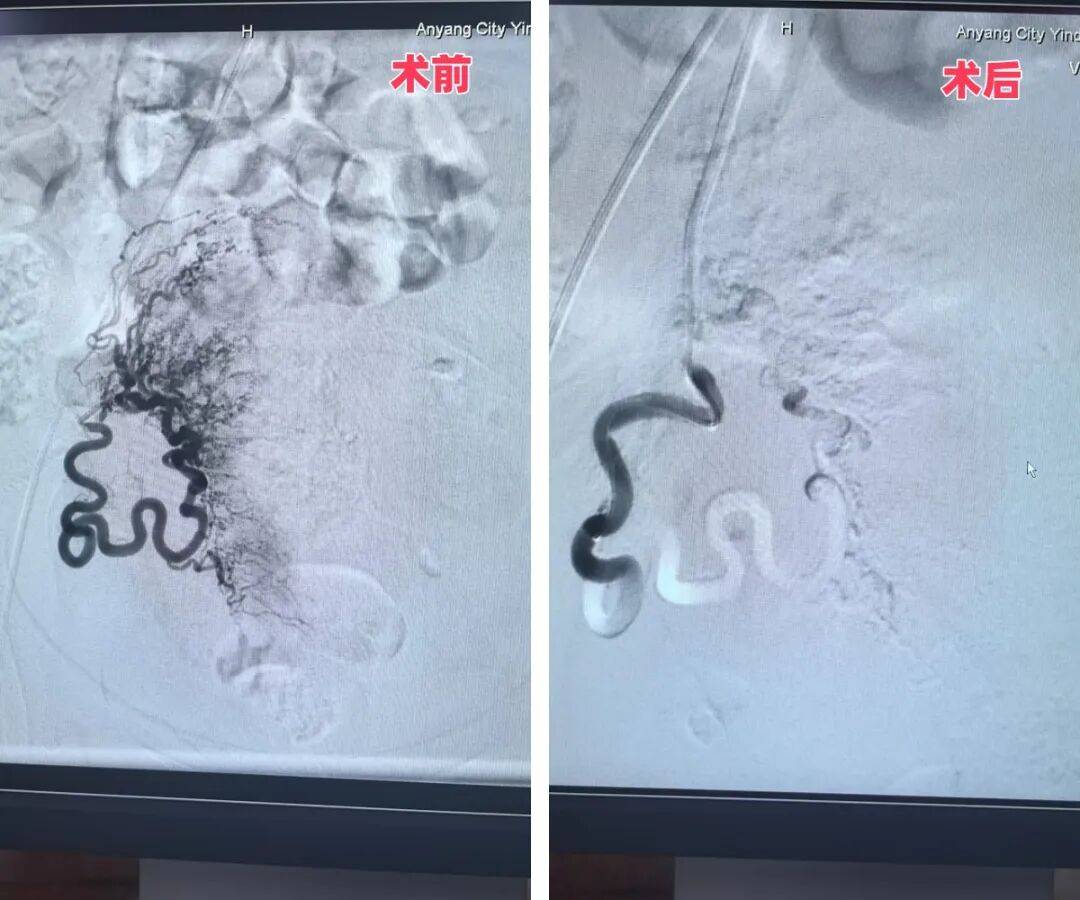

1月31日,殷都區(qū)人民醫(yī)院院長、介入專家魏棟親自操刀實(shí)施手術(shù)。憑借多年積累的豐富臨床經(jīng)驗(yàn),魏院長精準(zhǔn)完成雙側(cè)子宮動(dòng)脈栓塞操作,全程過程順利、定位精準(zhǔn),成功為患者筑起“止血防線”,大幅降低了后續(xù)手術(shù)的出血風(fēng)險(xiǎn)。此次雙側(cè)子宮動(dòng)脈栓塞術(shù),是殷都區(qū)人民醫(yī)院首次將介入技術(shù)應(yīng)用于婦科手術(shù),實(shí)現(xiàn)了相關(guān)診療領(lǐng)域的“零突破”。

左側(cè)子宮動(dòng)脈手術(shù)前后對比圖

右側(cè)子宮動(dòng)脈手術(shù)前后對比圖